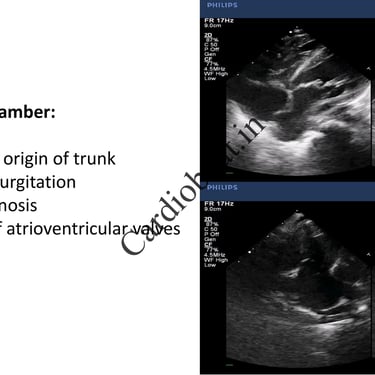

Truncus Arteriosus